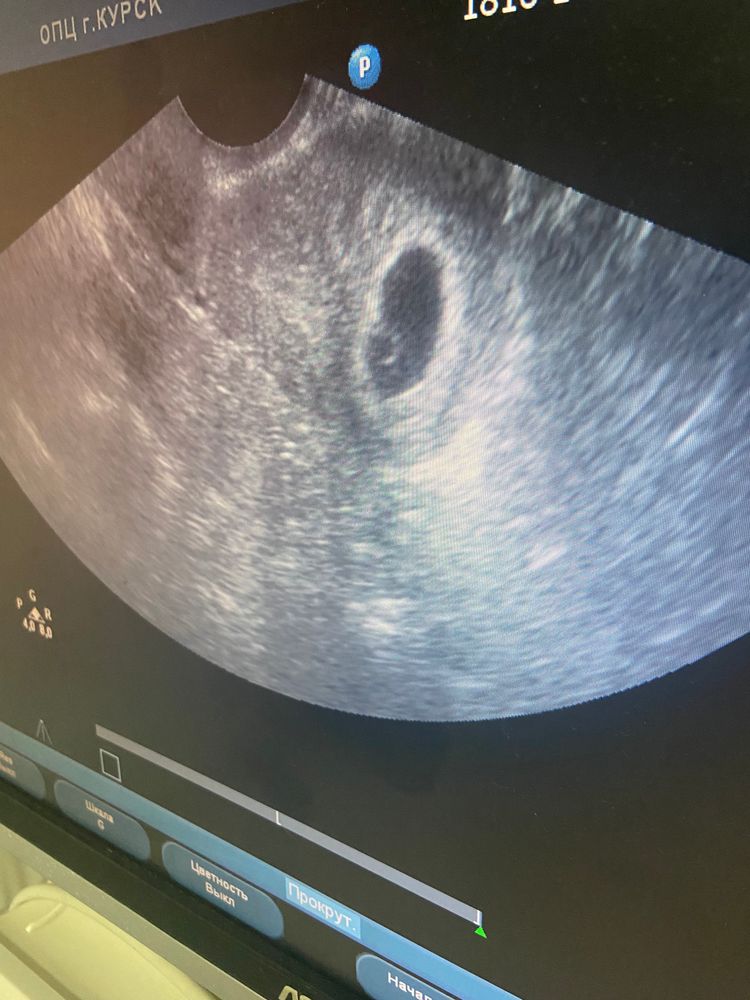

Результаты УЗИ23 дпп

Разрешили сфотографировать, плодное яйцо на месте

Эмбриончка пока не видно, позже схожу к своему врачу

Плодное яйцо d -14 мм, желточный мешочек 3 мм

Беременность 3.6 недель по плодному яйцу ♥️